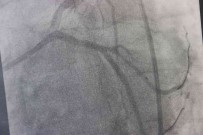

28 Ocak 2022 Cuma 09:56:51Fark Ettigi Küçük Kitleyi Ciddiye Almadi, Vücudundan 5 Kilogram Kitle Çikti

Karin bölgesinde sislik, yorgunluk gibi sikayetlerle hastaneye basvuran 56 yasindaki kadin vücudunda tespit edilen 5 kilogram agirligindaki kitlenin ameliyatla alinmasinin ardindan sagligina kavustu. 56 yasindaki Gülistan Altintas karin bölgesinde 6 yil önce küçük bir kitle tespit edildigini ancak kitleyi çok ciddiye almadigini söyleyerek çok pisman oldugunu söyledi. 6 yil önce tespit edilen kitle, 6 yil sonra 30 santimetre çapinda 5 kilo agirligina ulasti.